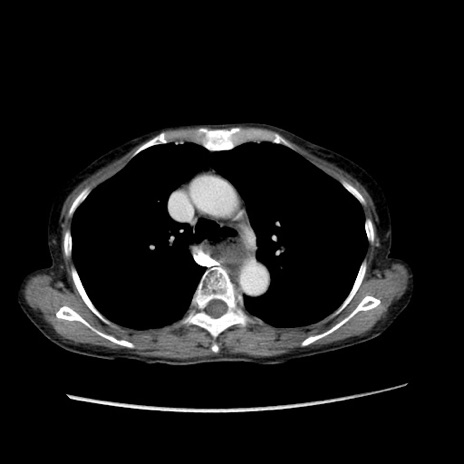

症例25(横断像)

【症例】80歳代女性

【主訴】胸のつかえ感

【現病歴】約9時間前に食後から胸のつかえた感じあり、嘔吐あり、来院。

【既往歴】胃癌(全摘)、胆摘、虫垂炎

【身体所見】心窩部に圧痛あり、反跳痛なし。

【データ】WBC 5700、CRP 0.05